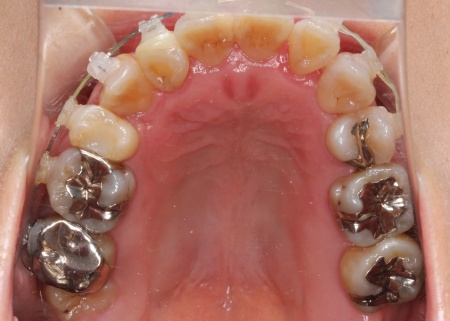

治療中